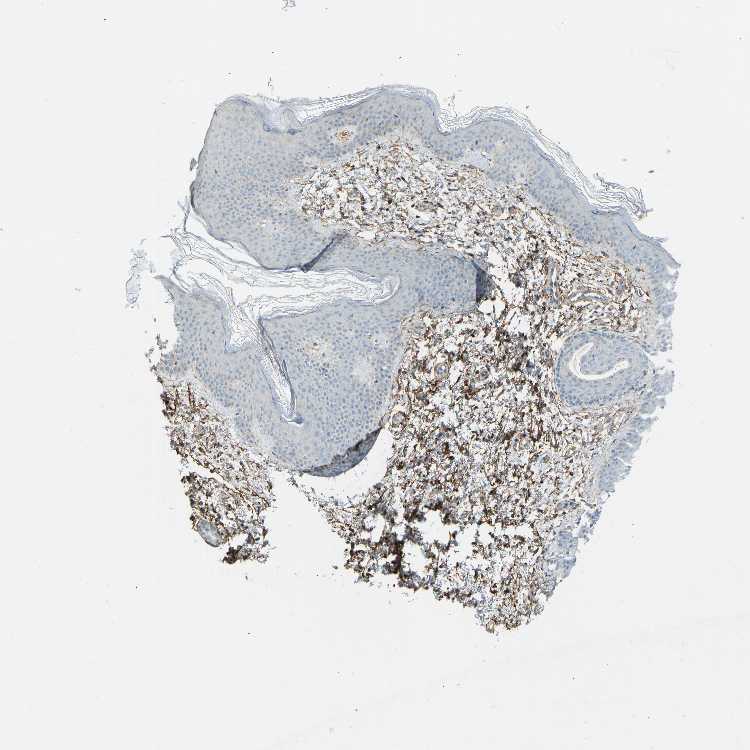

SKIN 1 - Antibody stainingi

Antibody staining in the annotated cell types in the current human tissue is reported as not detected, low, medium, or high, based on conventional immunohistochemistry profiling in selected tissues. This score is based on the combination of the staining intensity and fraction of stained cells.

Each image is clickable and will lead to virtual microscopy that enables deeper exploration of all samples and also displays staining intensity scores, fraction scores and subcellular localization as well as patient and tissue information for each sample.

Antibody HPA001934Antibody CAB018622

Endothelial cells High-

Extracellular matrix High-

Fibroblasts -Medium

Fibrohistiocytic cells High-